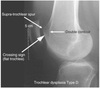

An 18-year-old man sustains a twisting injury to the left knee while playing football. An MRI scan is shown in Figure 48. What is the most likely diagnosis?

MRI scan shows a displaced, bucket-handle lateral meniscus tear. The sagittal view shows the typical “large anterior horn” sign, or “double meniscus” sign in which the displaced bucket-handle fragment appears just anterior to the native anterior horn of the lateral meniscus. The presence of the fibula on the sagittal view confirms this as the lateral compartment. The image is lateral and the cruciate ligaments are not visualized. The articular cartilage shown does not demonstrate an osteochondral lesion.